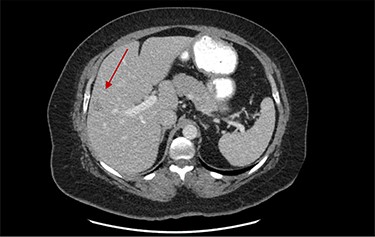

On assessment, the patient denied any symptoms related to her neuroendocrine tumor, including flushing, increased sweating, increased heart rate, wheezing, shortness of breath, diarrhea, weight loss or appetite changes. The only significant family history was a paternal and maternal grandfather with colon cancer. Imaging results were significant for computed tomography (CT) of chest demonstrating very small, but multiple, pulmonary nodules. A CT abdomen and pelvis demonstrated the known neuroendocrine tumor near the ileocecal valve (Fig. 1) as well as two poorly visualized liver lesions (Figs 2–4). The magnetic resonance imaging (MRI) demonstrated two separate one-centimeter lesions in segment 5 and 7 of the liver (Figs 5 and 6). The portal vein lacked normal left and right bifurcation; there was a circumferential right portal vein, which coursed anteriorly and superiorly and ultimately to the left lobe of the liver.